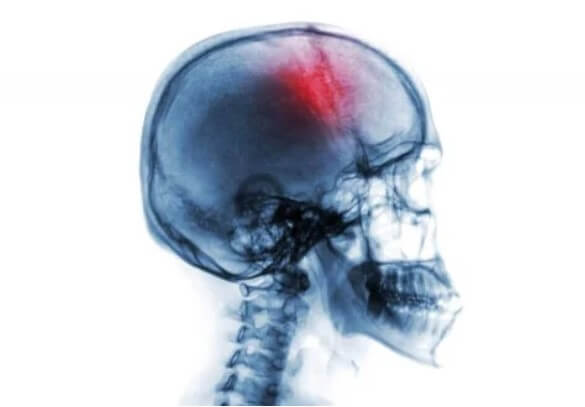

Το εγκεφαλικό επεισόδιο είναι ένα νευρολογικό σύνδρομο που εμφανίζεται ξαφνικά και συνοδεύεται από πολλούς παράγοντες κινδύνου και συμπτώματα. Περιλαμβάνει είτε αιμορραγία είτε απώλεια κυκλοφορίας αίματος στον εγκέφαλο.

Όταν η παροχή αίματος δεν φτάσει σωστά στον εγκέφαλο, τότε συμβαίνει ο θάνατος του εγκεφαλικού ιστού. Έτσι, οδηγεί σε ένα νευρολογικό έλλειμμα που μπορεί να οδηγήσει σε αναπηρία ή ακόμη και θάνατο.

- «Εγκεφαλικό» ή «εγκεφαλικό επεισόδιο». Αυτό συνεπάγεται διακοπή της ροής του αίματος στον εγκέφαλο. Πρώτον, μπορεί να προκληθεί από απόφραξη σε οποιοδήποτε από τα αιμοφόρα αγγεία που τροφοδοτούν τον εγκέφαλο (ισχαιμία). Αυτό συνήθως σχετίζεται με προβλήματα αθηροσκλήρωσης. Δεύτερον, μπορεί να οφείλεται σε ενδοεγκεφαλική αιμορραγία ή αιμορραγικό εγκεφαλικό επεισόδιο.